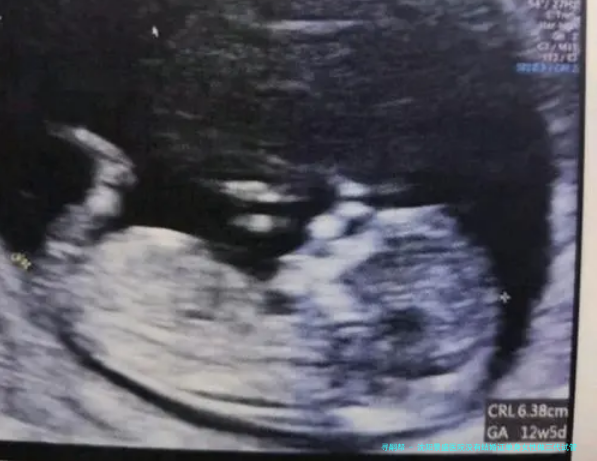

试管移植流程通常需要在促排卵期了结后进行。起首,医生会将检查筛选后的优良胚胎移植女性宫腔内。移植手术时间约为五至十分钟,麻醉形式为部分麻痹。术后患者须要躺床歇息两小时左右,观察身体状况。之后,患者须要定期监测受孕情况,并根据医生的指导进行后续的安胎护理。